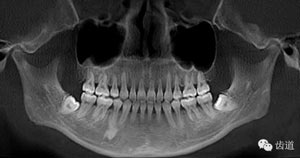

第三磨牙存,18與28牙冠小,38、48前傾阻生

中線不齊。未見(jiàn)明顯牙槽骨吸收。

治療后曲面斷層片

拔牙模式:患者25腭側(cè)完全錯(cuò)位后左上磨牙前移,使左側(cè)磨牙關(guān)系接近完全遠(yuǎn)中,而28牙冠較小,故正畸矯治拔除了14,18,25,28,35,45,于上頜第一與第二磨牙間頰腭側(cè)各植入微種植體支抗,運(yùn)用微種植體支抗壓低上磨牙,內(nèi)收前牙并糾正中線,適當(dāng)遠(yuǎn)中移動(dòng)左上牙列。下頜第三磨牙矯治前并未拔除是因?yàn)槠渖L(zhǎng)對(duì)矯治有利,建議其矯治后拔除。